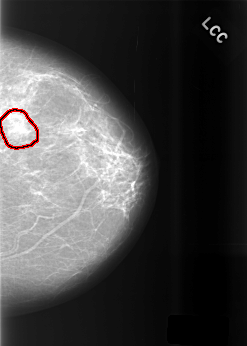

C_0469_1.LEFT_CC

LEFT_CC LINES 5536 PIXELS_PER_LINE 3944 BITS_PER_PIXEL 12 RESOLUTION 50 OVERLAY

FILE: C_0469_1.LEFT_CC.OVERLAY

TOTAL_ABNORMALITIES 1

ABNORMALITY 1

LESION_TYPE MASS SHAPE FOCAL_ASYMMETRIC_DENSITY MARGINS N/A

ASSESSMENT 3

SUBTLETY 4

PATHOLOGY BENIGN_WITHOUT_CALLBACK

TOTAL_OUTLINES 1

BOUNDARY